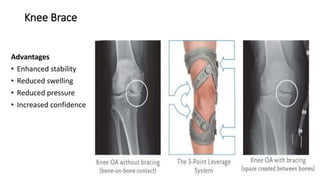

Knee Brace

Advantages

• Enhanced stability

• Reduced swelling

• Reduced pressure

• Increased confidence

Knee adduction moment (KAM) during gait is known to indicate disease severity and prognosis of

varus knee Thus, to reduce KAM is a key strategy in treatment of knee OA.

KAM is primarily calculated as the product of the resultant ground reaction force (GRF) in the frontal

plane and the perpendicular distance from the GRF to the knee joint center (frontal plane lever arm).